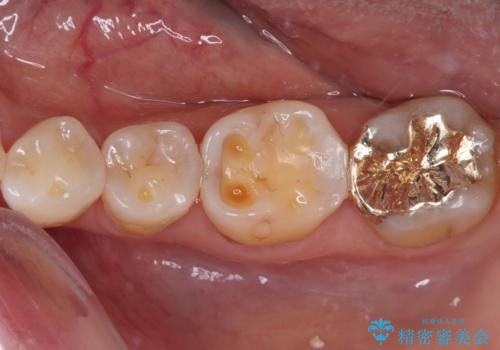

奥歯の銀歯をゴールドでしっかりと治療

ゴールドは「白い歯」ではありませんが、銀歯の金属色とは異なり、非常にきれいな色合いが特徴です。

もちろん、適合が極めて良いという圧倒的メリットもゴールドクラウンやゴールドインレーの特徴です。